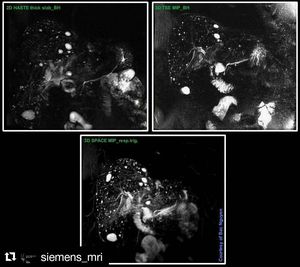

MRCP techniques at 3 Tesla, Siemens Skyra. Different approach to visualize the bile duct system. Varies in scantime and resolution. Use these techniques properly to answer the clinical questions